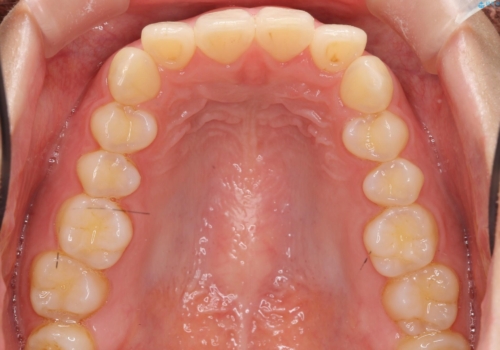

下の前歯が1本短い インビザラインと部分矯正の組み合わせ

- 前歯のガタつきと、下の前歯が一本短いことを主訴に来院。

インビザラインのマウスピースではめる装置で歯を引っ張り出すことは難しいと説明し、下の前歯だけワイヤー部分矯正を行ってからインビザライン矯正で仕上げをしました。

難しい部分を短期間ワイヤー矯正を行ってからのインビザラインは、全体治療が短くなるだけでなく、仕上がりもよくなるのでオススメです。